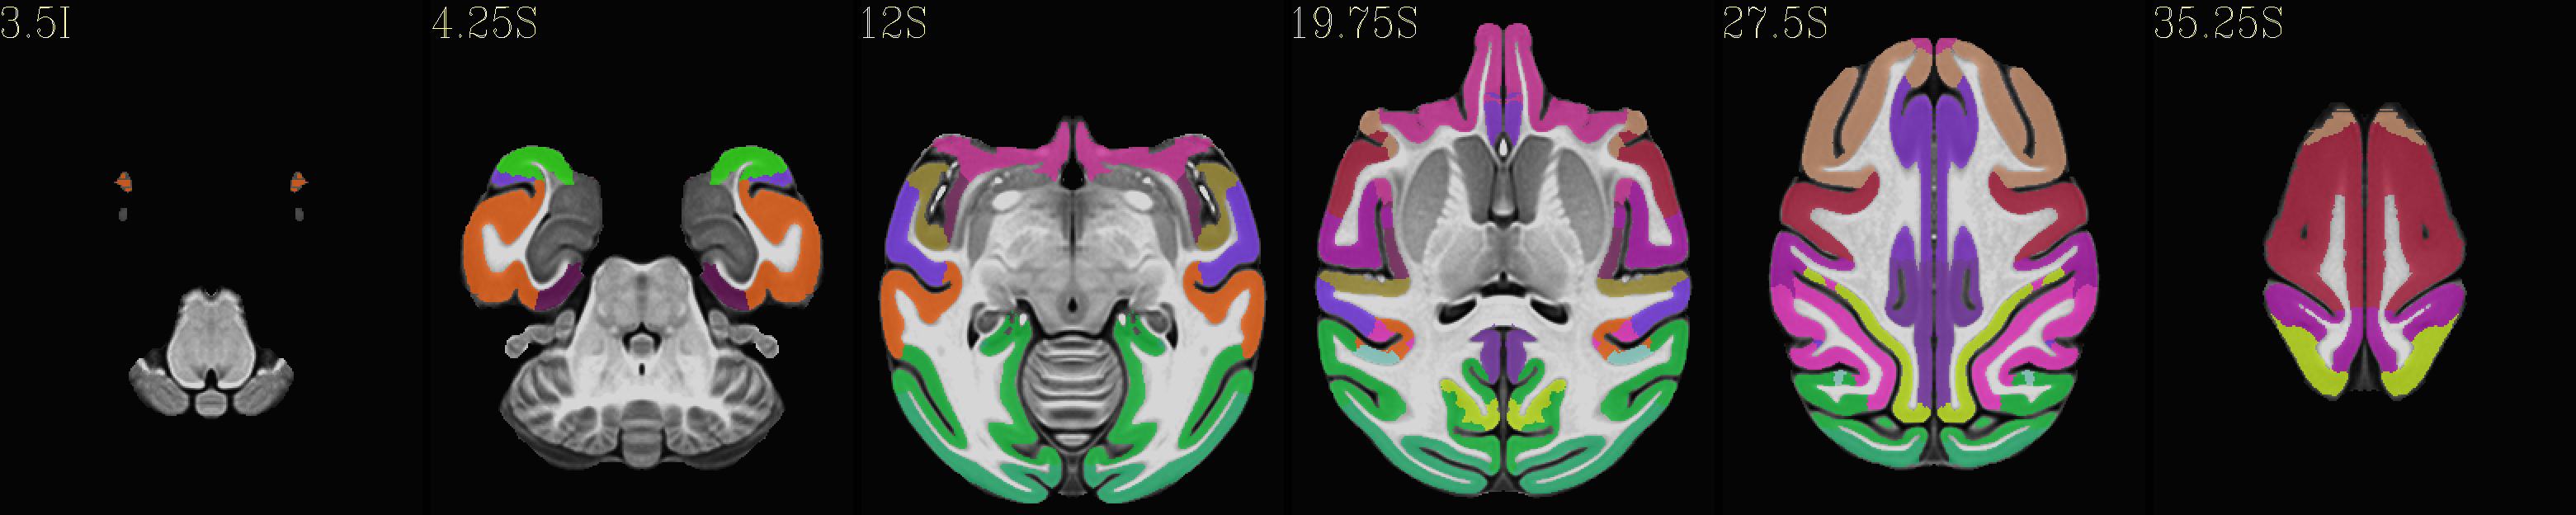

The following images were made using the symmetric NMT v2 template (with “standard” spatial resolution = 0.25 mm, and FOV = brain volume) and accompanying CHARM.

Skull-stripped NMT with the CHARM (level 5)

../../_images/img_nmt2.0symss_charmL5.axi.png

../../_images/img_nmt2.0symss_charmL5.cor.png

../../_images/img_nmt2.0symss_charmL5.sag.png

Skull-stripped NMT with the CHARM (level 6)

../../_images/img_nmt2.0symss_charmL6.axi.png

../../_images/img_nmt2.0symss_charmL6.cor.png

../../_images/img_nmt2.0symss_charmL6.sag.png